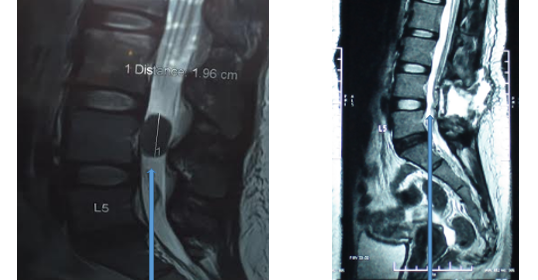

倪小姐被轉介接受物理治療進行牽引拉腰,但做完牽引後腳痛立刻加劇,痛楚還伸延至胝骨、尾骨及腳面,腳部無力連走路都非常困難,病人當晚自行到私家醫院接受磁力共振掃描,結果報告顯示腰椎第四節椎管內長了一個很大的脊膜瘤(Meningioma)並壓着馬尾神經線,引致患者的感覺神經及肌力神經出現缺損現象。除了脊膜瘤,病者還有腰椎第五節椎間盤突出的跡象。